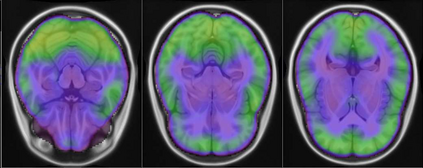

Representational similarity analysis (RSA) is a multivariate technique to investigate cortical representations of objects or constructs. While avoiding ill-posed matrix inversions that plague multivariate approaches in the presence of many outcome variables, it suffers from the confound arising from the non-orthogonality of the design matrix. Here, a partial correlation approach will be explored to adjust for this source of bias by partialling out this confound. A formal analysis will show the dependence of this confound on the temporal correlation model of the sequential observations, motivating a data-driven approach that avoids the problem of misspecification of this model. However, where the autocorrelation locally diverges from the volume average, bias may be difficult to control for exactly (local bias), given the difficulties of estimating the precise form of the confound at each voxel. Application to real data shows the effectiveness of the partial correlation approach, suggesting the impact of local bias to be minor. However, where the control for bias locally fails, possible spurious associations with the similarity matrix of the stimuli may emerge. This limitation may be intrinsic to RSA applied to non-orthogonal designs.